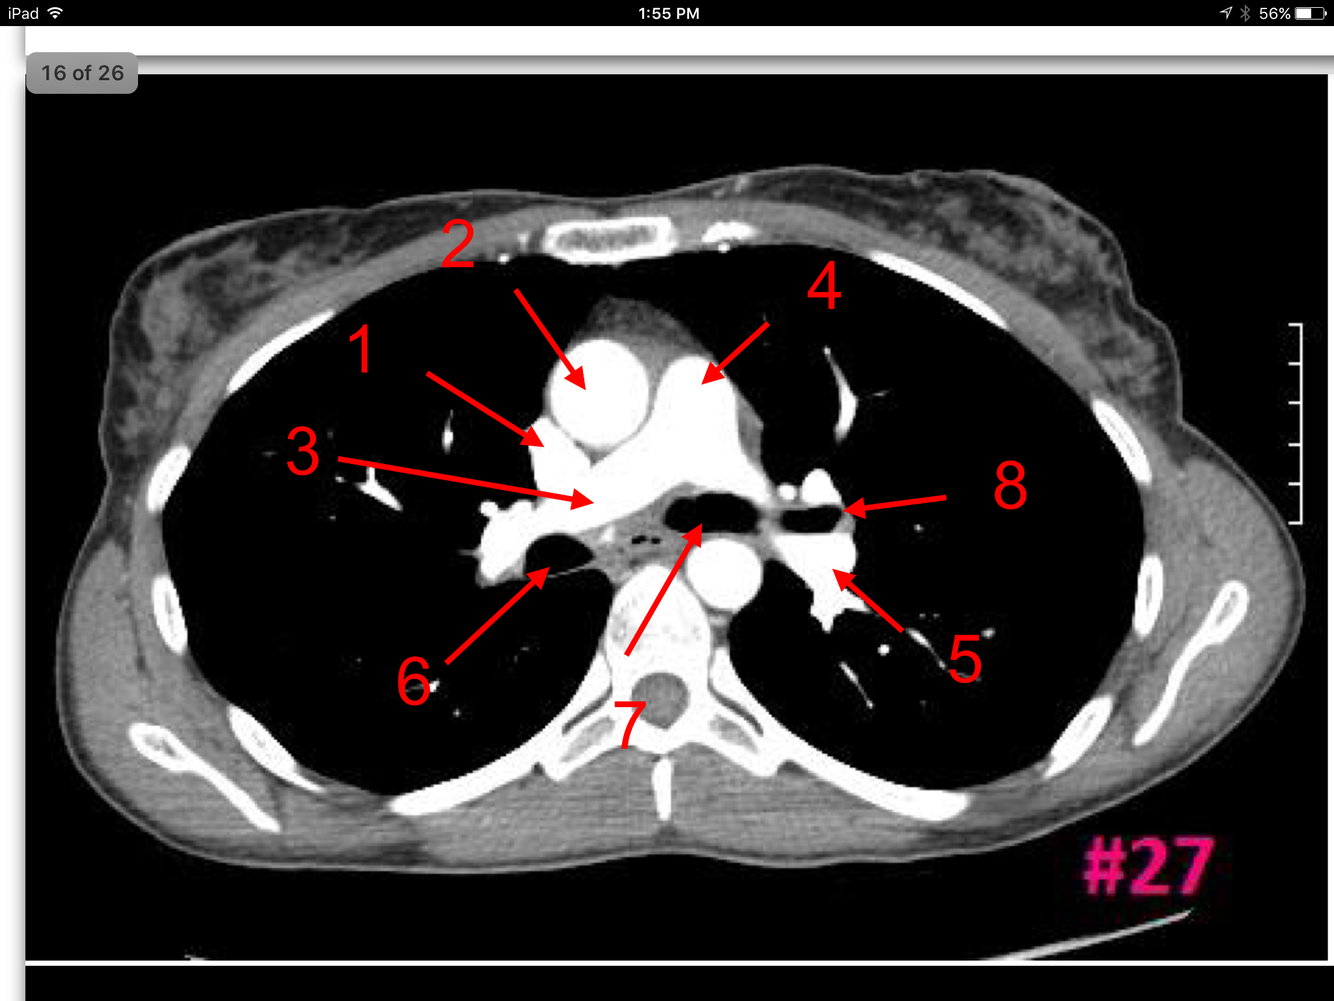

16

A

Superior vena cava

Ascending aorta

Rt pulmonary artery

Pulmonary trunk

Lt pulmonary artery

Rt main bronchus

Lt main bronchus

Lt superior lobar bronchus